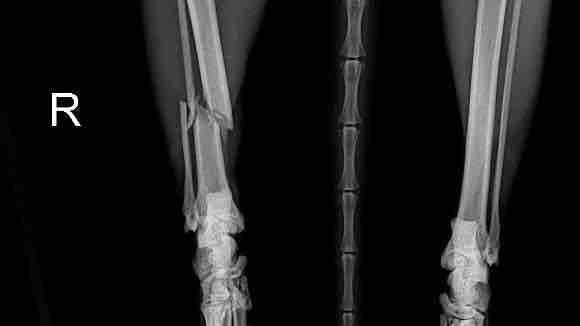

骨折脫臼與發育異常的矯正

結合影像學、理學檢查與運動力學,提出適合的骨科治療方案

也許是車禍、也許是玩樂時不小就跛腳了,究竟只是扭傷,還是骨折脫臼?需要正確的X光診斷,判斷傷勢,再結合運動力學,規劃合適的骨科手術方案,避免只吃止痛藥造成永久性的傷害,再配合術後正確的照顧與復健,讓毛小孩重獲行動的自由。